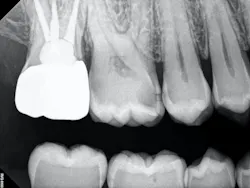

The carious tissue was removed, followed by the endodontic procedure and subsequent placement of the build-up. Despite the deep extent of mesial decay, a clear and accurate scan was achieved (figure 2).